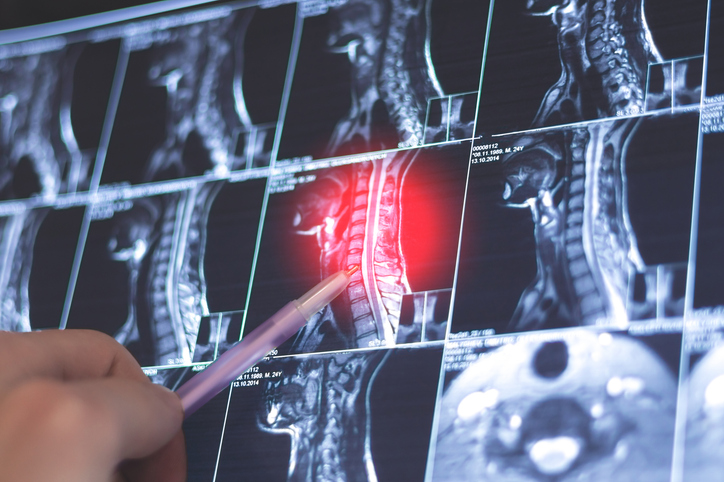

Head and neck cancer has a wide range of treatment options, which depend on the cancer’s type, location, and stage. Treatment is often multimodal, involving surgery, radiation, and systemic therapies like chemotherapy or immunotherapy. Diagnosis typically begins with a biopsy and imaging, and patients usually work with an ENT specialist, medical oncologist, and radiation oncologist.

Because the head and neck contain many vital structures, treatment can be especially challenging. Radiation, in particular, can cause side effects such as mouth and throat pain, taste changes, dry mouth, thick saliva, and difficulty swallowing—often requiring feeding tubes and dietary support. A strong care team, including a dietitian, plays a vital role in helping patients through this intensive process.

“There have been a lot of advancements in the field of head and neck cancer over the years, and it's greatly deescalated treatment-related effects. It can be a very difficult treatment to get through. But, there have been a lot of surgical advances, as well as studies on immunotherapy and targeted therapies,” assures Swanson. “For radiation, the goal is to target the cancer with precision and minimize the damage to healthy tissues. It's really focused on improving their quality of life before, during, and after treatment without compromising their cure rate or outcomes.”